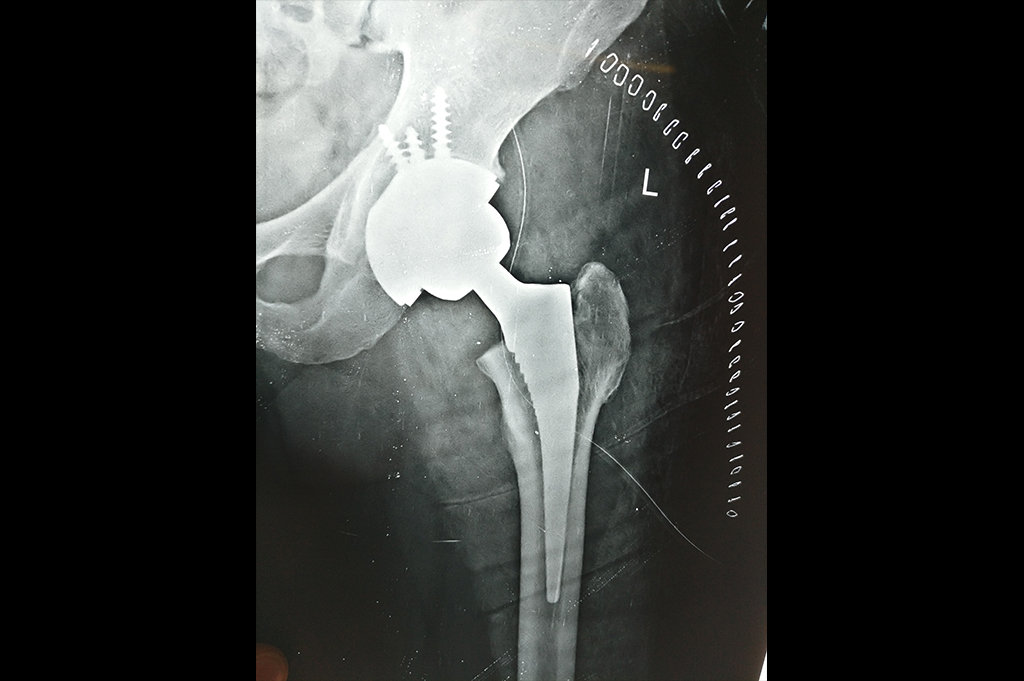

Total Hip Replacement - THR